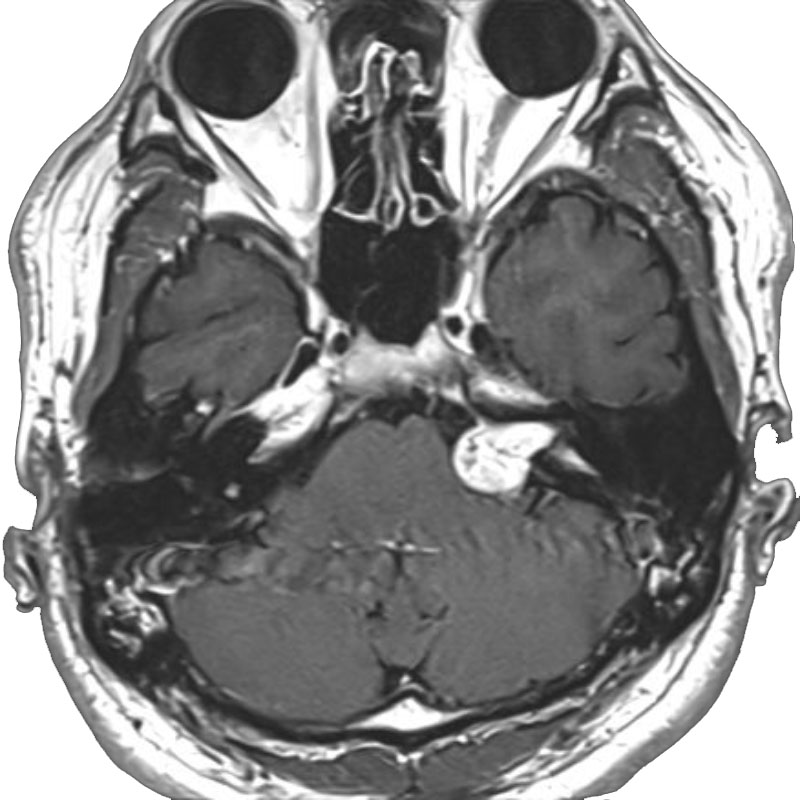

左椎骨動脈狭窄症

頚胸椎後方固定

乾/長尾/殿元/青木